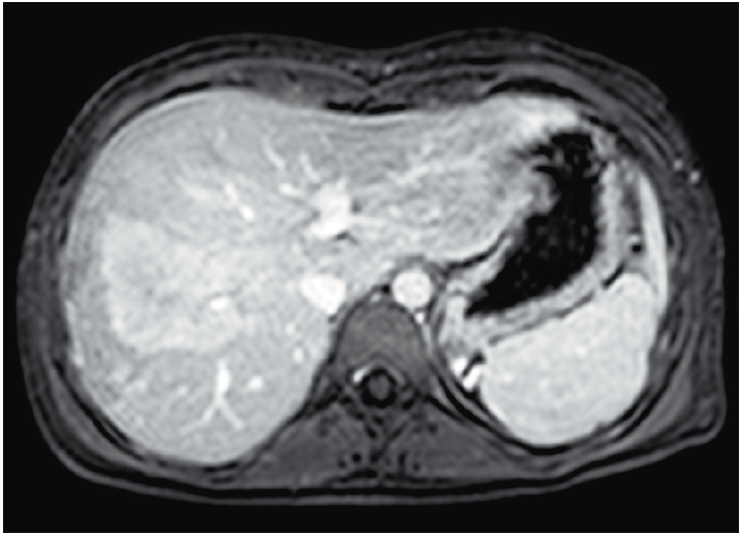

Figura 2c. Imagen de resonancia magnética ponderando secuencia T1

con supresión grasa tras la administración del contraste, que demuestra un refuerzo moderado y

heterogéneo de la lesión con menor realce central. Se puede apreciar un sector de la vena suprahepática

media atravesando el seno de la masa